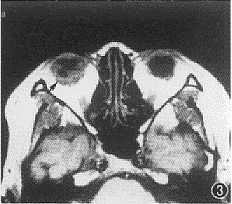

3 MRI 检查眼内囊尾蚴病 (活动期),T1加权像玻璃体后部呈中等信号, 其内可见低信号囊泡影及中低信号头节影 (箭头)